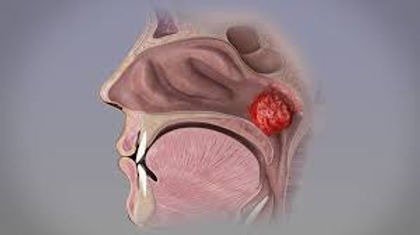

Is your child struggling with constant nasal blockage, snoring, mouth breathing, or recurrent ear infections? Enlarged or infected adenoids could be the reason. At my ENT clinic in Delhi, I offer safe and effective adenoidectomy surgery, a proven solution to help children (and sometimes adults) breathe better, sleep soundly, and stay healthier.

Adenoidectomy is a surgical procedure to remove the adenoids—a mass of lymphoid tissue located at the back of the nasal passage. While adenoids play a role in fighting infections in early childhood, they can become chronically enlarged or infected, leading to a range of issues, especially in young children.

This simple procedure is often performed when enlarged adenoids interfere with breathing, sleeping, or ear health, and when medical treatments fail to provide long-term relief.

With over 10 years of experience in ENT care, I provide specialized pediatric and adult adenoid surgery using advanced, minimally invasive techniques. The procedure is typically done under general anesthesia, lasts only 30–45 minutes, and most children go home the same day.